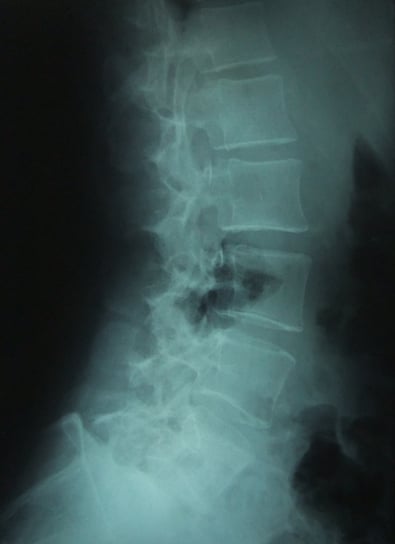

脊柱起立筋の慢性的緊張、仙腸関節の動きがない。

腰椎過前弯・仙骨角・仙腸関節・治らないのではないかという不安による慢性的交感神経緊張